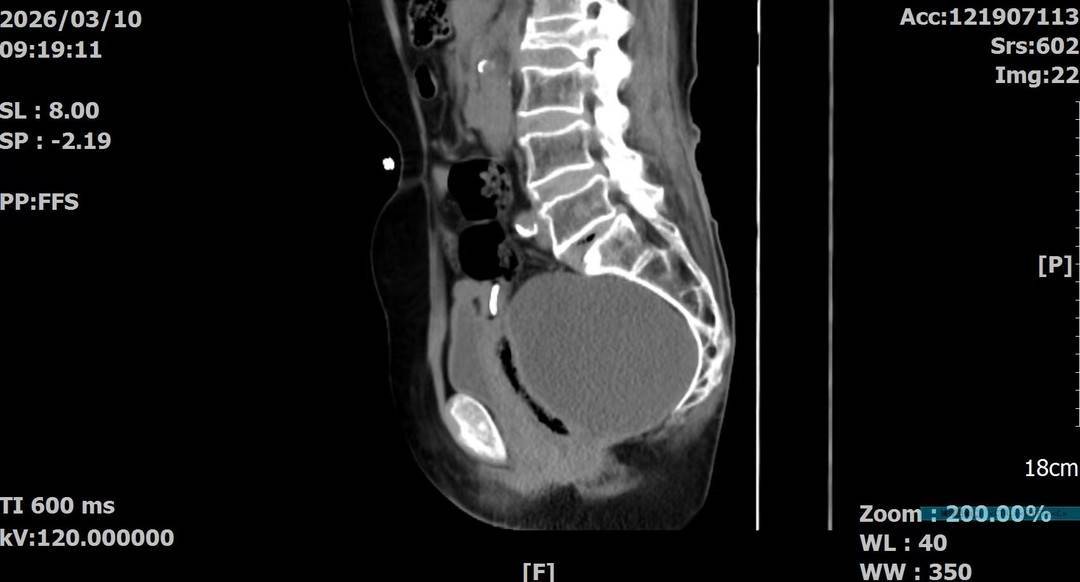

王女士近期感觉腹部不适,检查后发现盆腔内竟藏着一个巨大的包块。CT影像显示,这颗肿瘤直径约14厘米,位置极其刁钻——它位于骶前区域。在医生眼中,这里被称为妇科手术的“高危禁区”。肿瘤后方紧挨着骶前静脉丛,一旦损伤可能引发致命的大出血;前方是直肠,两侧是输尿管。对于一位77岁的高龄老人来说,要在这个“雷区”里做手术,风险不言而喻。